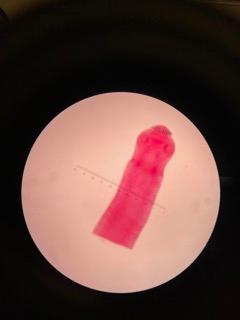

Clonorchis adult